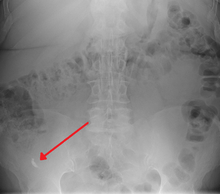

| A fecolith marked by the arrow which has resulted in acute appendicitis. | |

Fecolith, also called a fecaloma or faecaloma, is an extreme form of fecal impaction, often characterized by calcification. The term fecalith literally means a "stone" made of feces (lith=stone). It is a hardening of feces into lumps of varying size and may occur anywhere in the intestinal tract but is typically found in the colon. It is also called appendicolith when it occurs in the appendix and is sometimes concomitant with appendicitis.[1] They can also obstruct diverticuli.

Fecal impaction and attempts at removal can have severe and even lethal effects, such as the rupture of the colon wall by catheter or an acute angle of the fecaloma (stercoral perforation), followed by septicemia. A small fecalith is one cause of both appendicitis and acute diverticulitis. It may also lead to stercoral perforation, a condition characterized by bowel perforation due to pressure necrosis from a fecal mass or fecaloma.[7][8]